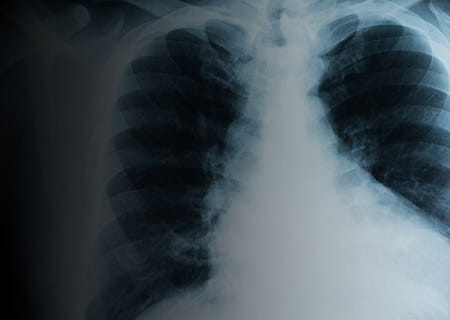

The cancer experts at UH Seidman Cancer Center use a variety of tools to detect and diagnose cancer. Bloodwork and other lab tests, imaging technology (such as CT, MRI, PET and ultrasound) and biopsies are all used to diagnose cancer and determine the cancer’s stage (whether it has spread to other areas of the body.)

Lung Cancer Screening Program

UH offers a lung cancer screening program for patients who are at high risk for developing lung cancer.